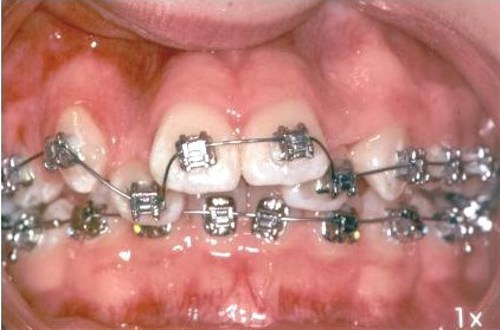

En fast bøjle består af små brackets, som limes fast på tænderne. Tværs over tænder og brackets sættes en bue i metaltråd ("togskinner"). Den faste bøjle kan kun sættes på og fjernes på tandklinikken.

Billederne nedenfor viser en fast bøjle og en sektionsbue, som er en fast bøjle over nogle få tænder.